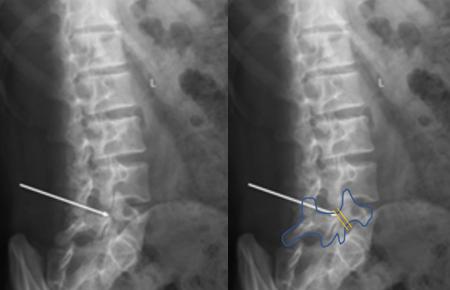

孩子总说腰痛,如何确定是不是峡部裂,有没有滑脱?广州中医药大学第一附属脊柱骨科唐晶晶博士介绍,腰椎X线片检查是最简便、廉价的诊断方法,有多种不同的X线片拍摄方法,包括正位、侧位、斜位。其中在斜位片上出现的透光带常常被称为“狗脖子断裂”。

X光片上会出现“狗脖子断裂” 图/受访者提供

尽管斜位片对峡部的缺损最为敏感,但侧位片最适合观察滑移的程度。